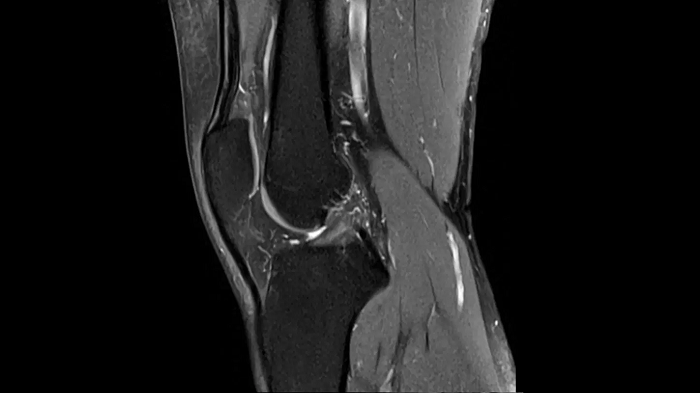

Elbow

T2 TSE with Deep Resolve

Exceptional performance for small joints owing to Deep Resolve.

Deep Resolve Gain & Sharp

0.3 x 0.3 x 3.0 mm2

TA 2:54 minutes

MAC-ID: 7aaaa0190.

MAC-ID: 7aaaa0190. Image Credit: Siemens Healthineers

T1 TSE with Deep Resolve

Thanks to Simultaneous Multi-Slice and Deep Resolve, an exceptional performance for small joints is possible.

SMS 2 | Deep Resolve Gain & Sharp

TA 2:15 minutes

PD TSE Fat Sat with Deep Resolve

Thanks to Deep Resolve, outstanding performance for small joints is possible.

TA 3:43 minutes